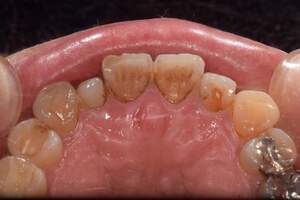

歯石除去

治療前

治療後

| 年齢 | 43歳・男性 |

| 主訴 | 歯石をとりたい |

| 治療内容 | 歯石除去 |

| 治療期間 | 30分 |

| 費用 | 約2,000円 |

| リスク・副作用 | ・歯ぐきの炎症が強いと歯石を取る際に出血することがあります ・処置後に歯がしみることがあります ・歯と歯の間に隙間ができるので、息が漏れ発音しにくいと感じることがあります ・歯ぐきの炎症が軽減すると歯ぐきが引き締まり、歯が長く見えることがあります |